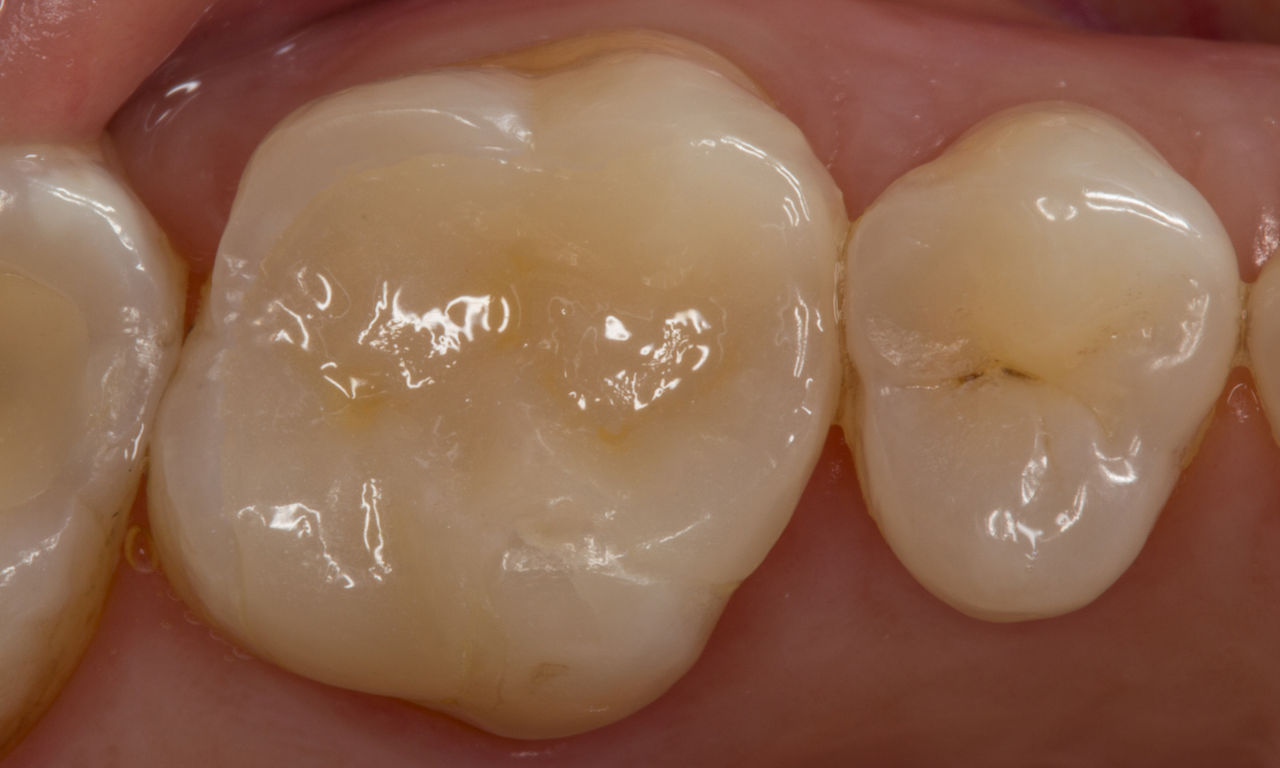

Before: Pre-operative clinical scenario after endodontic therapy.

After: 1 month after the CEREC Tessera onlay was bonded.